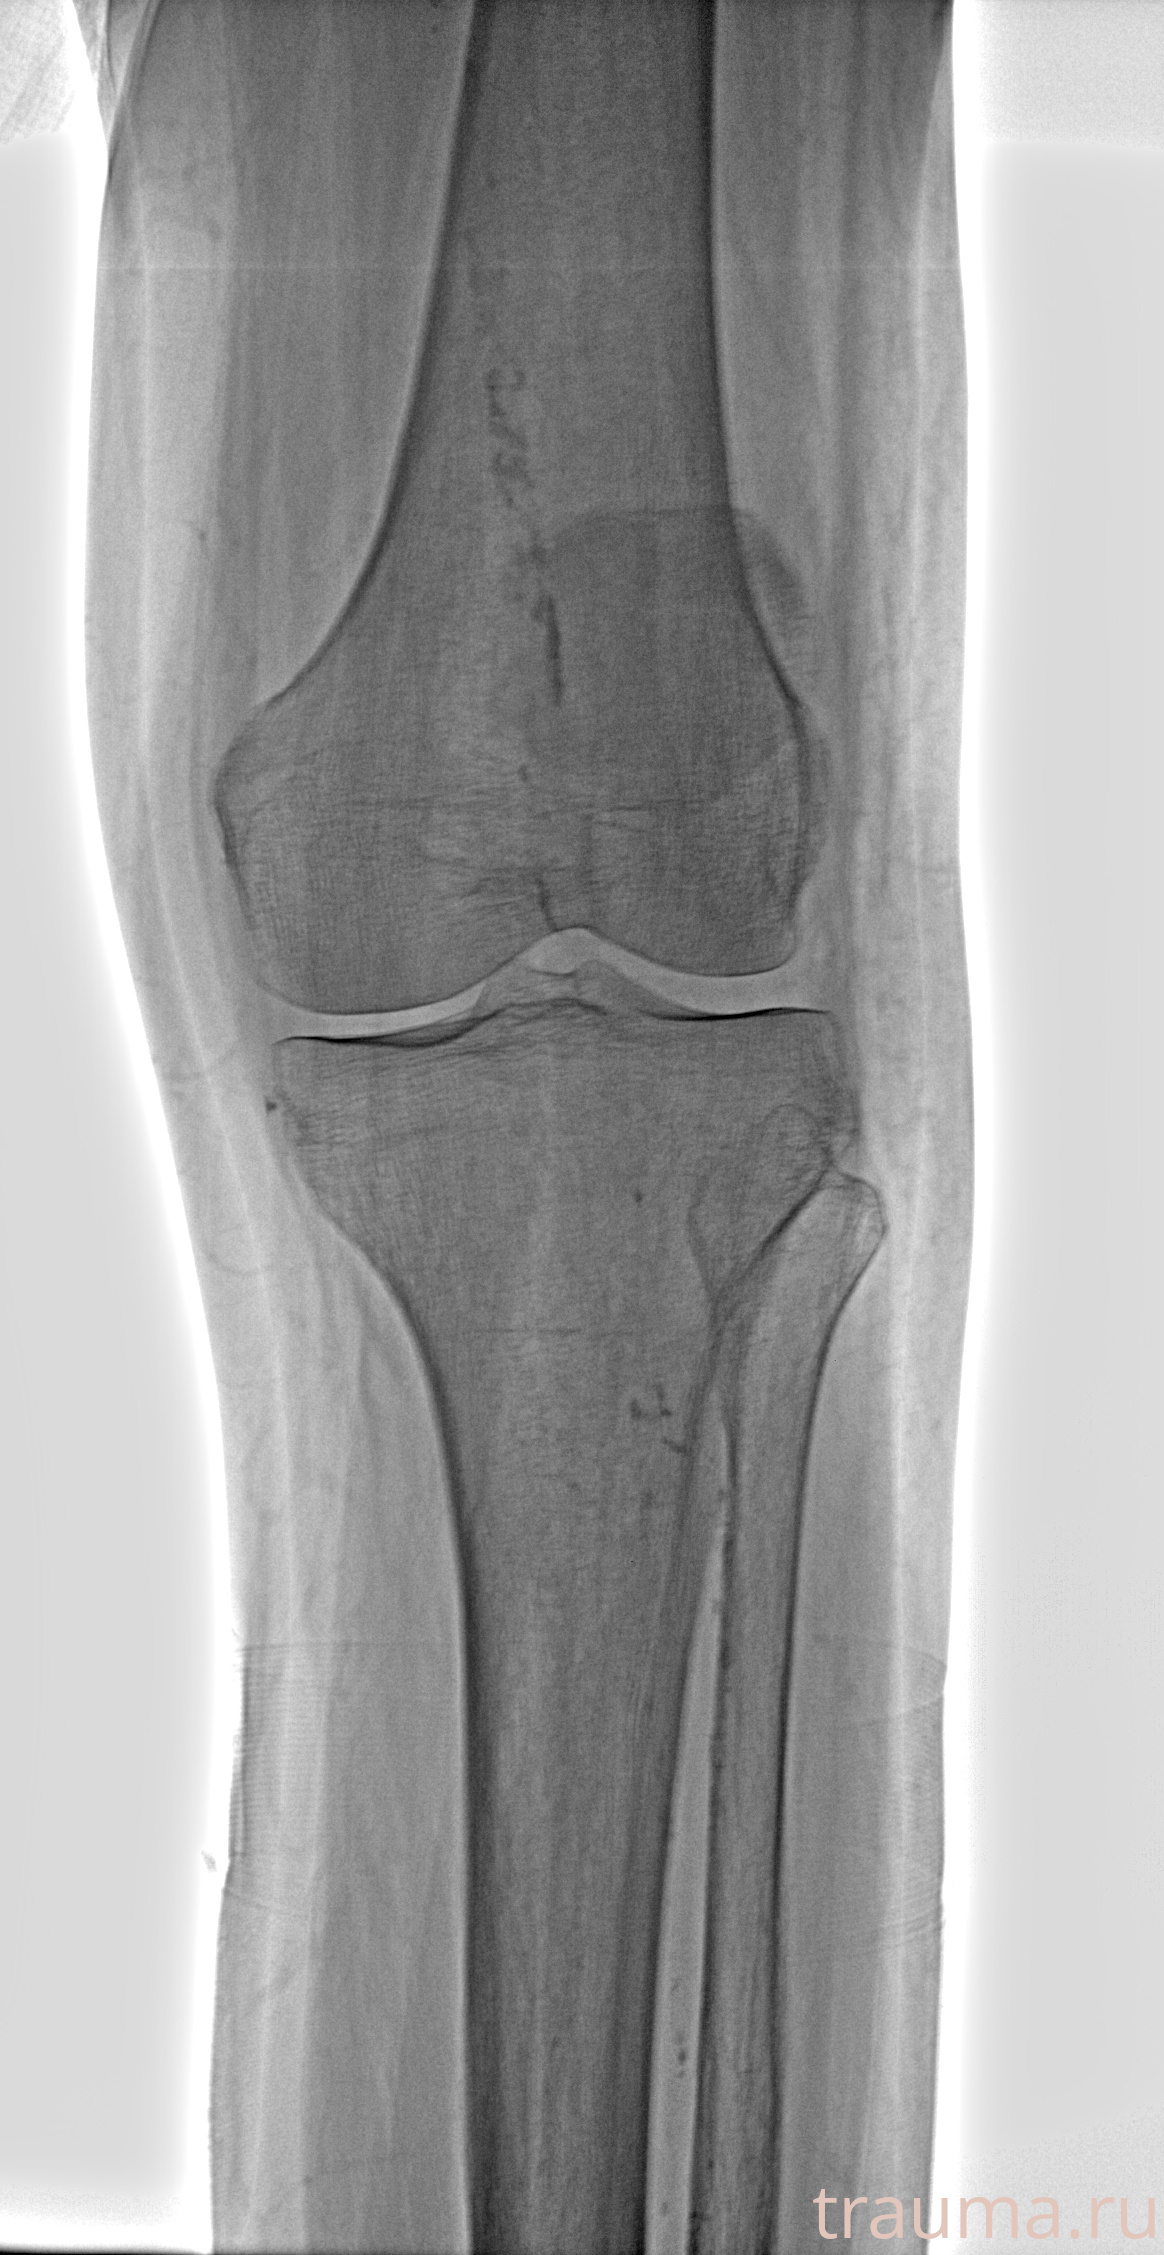

Рентгенограммы

Рентген на дому: по вашему адресу приезжает врач-рентгенолог, травматолог-ортопед с мобильным рентгеновским аппаратом, проводит диагностику травмы или заболевания, делает необходимые рентгенограммы, дает рекомендации по дальнейшему лечению. Получить качественные снимки в домашних условиях возможно благодаря уникальной методике, разработанной МосРентген Центром для института  Склифосовского